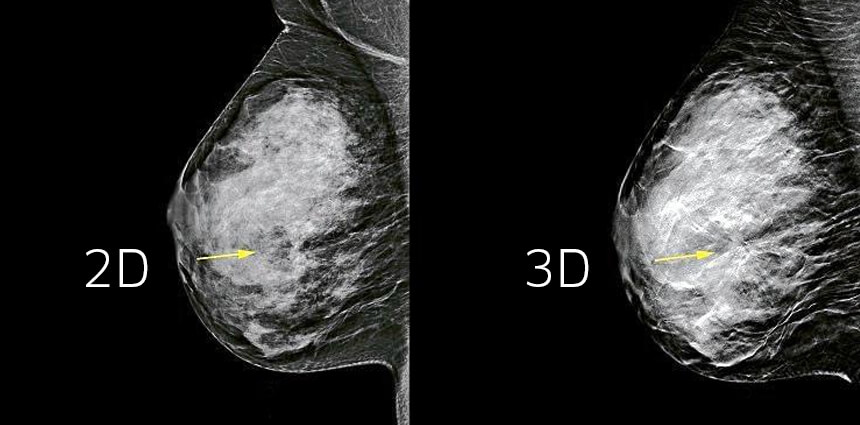

Just like a three-dimensional photo is more detailed and lifelike than a 2D image, digital breast tomosynthesis (DBT)—or 3D mammography—gives radiologists a clearer view of breast tissue. And that's why this new technology has rapidly become an essential imaging tool that enhances a doctor's ability to detect early breast cancer. With breast cancer, earlier detection leads to earlier treatment, less aggressive treatment options, and better outcomes.

Thanks to 3D mammography, radiologists can view breast images in "slices," which essentially allows them to see straight through tissue layers and makes it less likely they’ll miss an early sign of cancer. Unlike 2D mammograms, the 3D technology also makes it easier for radiologists to detect breast cancer that is masked by overlapping fibroglandular tissue. Research shows 3D mammography is up to 40 percent better at detecting invasive breast cancers.

“When you take a traditional mammogram, you are taking a picture of a 3D object and producing a 2D representation,” Dr. Priyanka said. “As a result, you have structures that sit on top of each other and mimic a mass.” With 3D, the doctor can go in and view each “slice” of the breast to determine if it is a mass. “Ultimately it means that our ability to pick up small cancers is improved, and we have fewer false positives,” explained Dr. Priyanka.